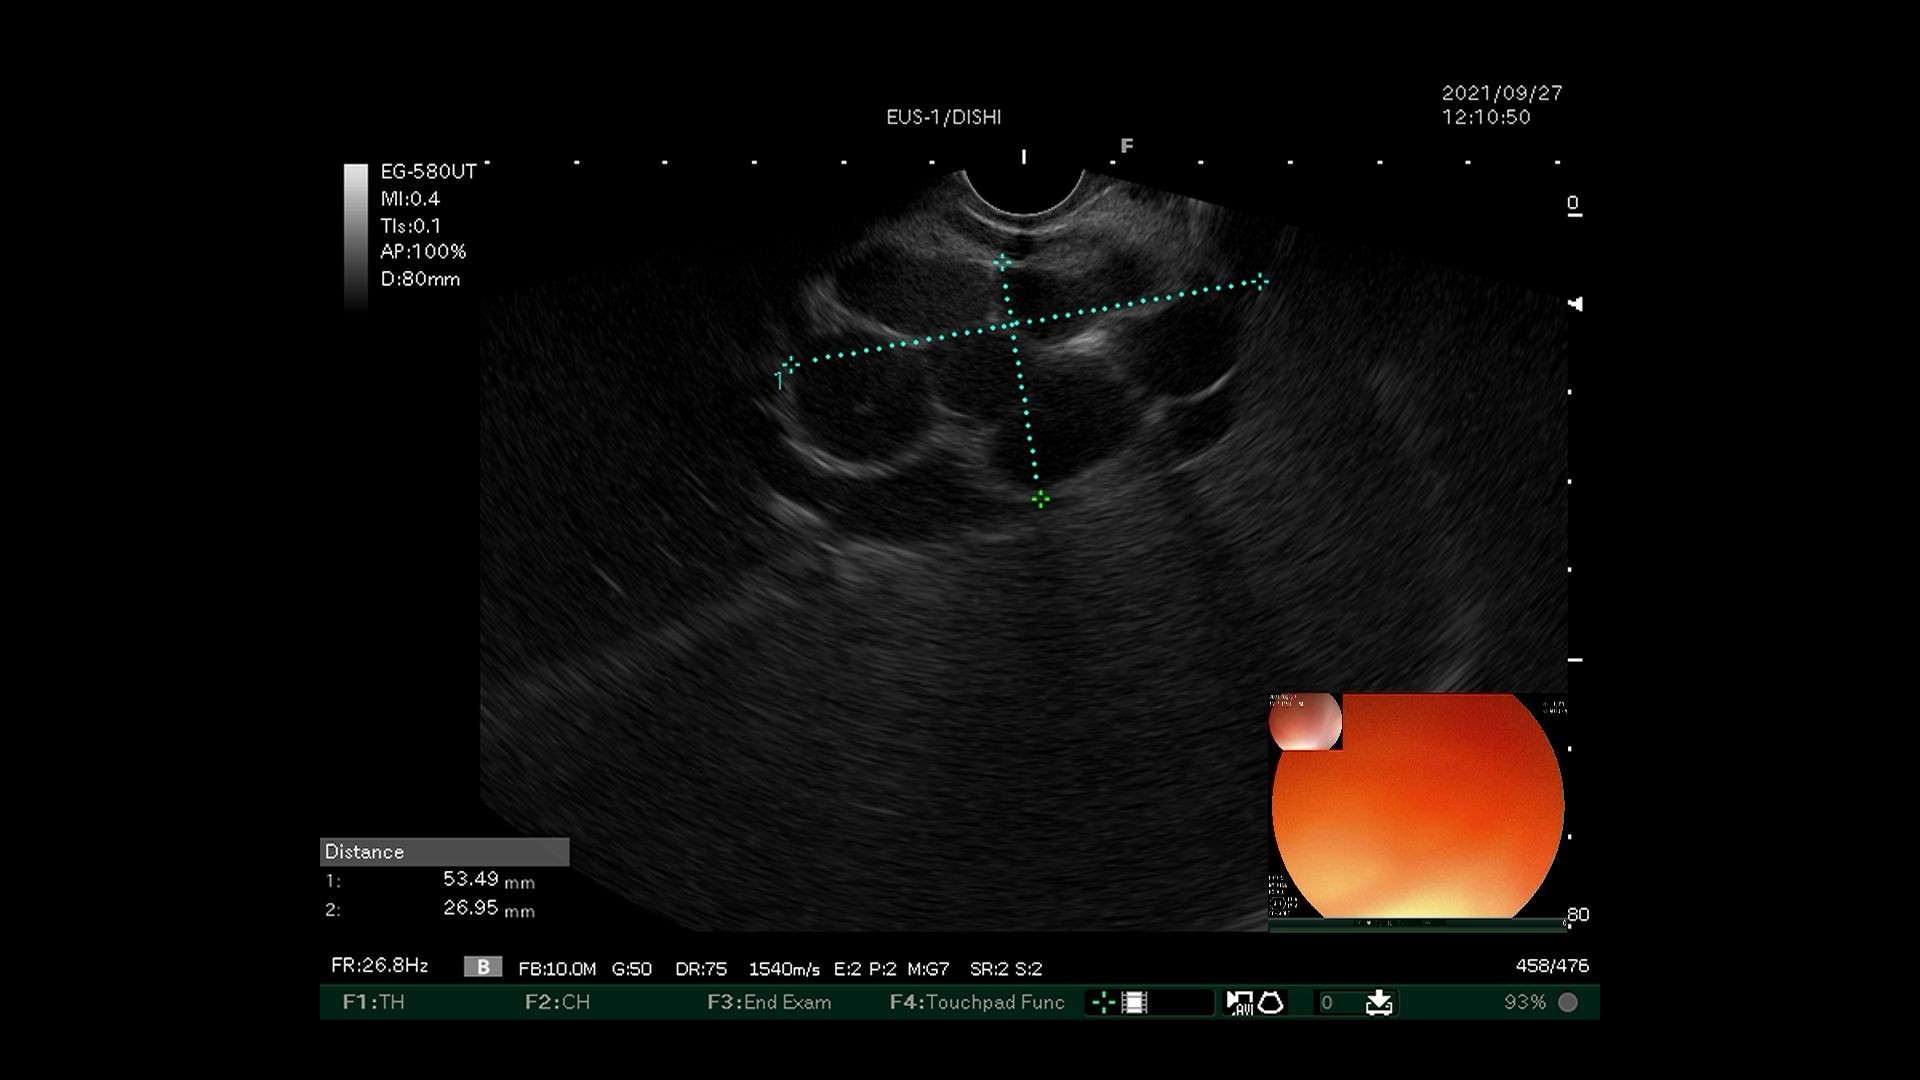

2)超声内镜探查食管下段近贲门处,发现曲张静脉并测量直径。